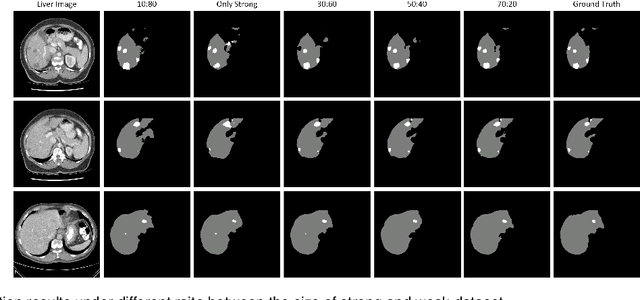

Abstract:Synthesizing a subject-specific pathology-free image from a pathological image is valuable for algorithm development and clinical practice. In recent years, several approaches based on the Generative Adversarial Network (GAN) have achieved promising results in pseudo-healthy synthesis. However, the discriminator (i.e., a classifier) in the GAN cannot accurately identify lesions and further hampers from generating admirable pseudo-healthy images. To address this problem, we present a new type of discriminator, the segmentor, to accurately locate the lesions and improve the visual quality of pseudo-healthy images. Then, we apply the generated images into medical image enhancement and utilize the enhanced results to cope with the low contrast problem existing in medical image segmentation. Furthermore, a reliable metric is proposed by utilizing two attributes of label noise to measure the health of synthetic images. Comprehensive experiments on the T2 modality of BraTS demonstrate that the proposed method substantially outperforms the state-of-the-art methods. The method achieves better performance than the existing methods with only 30\% of the training data. The effectiveness of the proposed method is also demonstrated on the LiTS and the T1 modality of BraTS. The code and the pre-trained model of this study are publicly available at https://github.com/Au3C2/Generator-Versus-Segmentor.